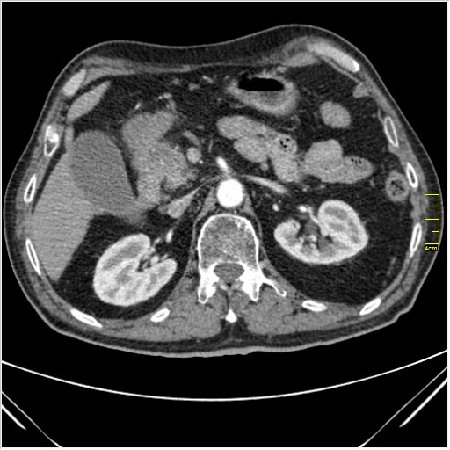

Мужчина 62 года с желтухой

Опухоль головки поджелудочной железы, расширение холедоха и панкреат. протока (Double Channel sign)

Карциномы панкреас гиподенсны на КТ с болюсом, т.к. содержать много соединительной и фиброзной ткани, в отличие от нормальной ткани железы, которая (как любая железа) хорошо васкуляризирована. Поэтому если видим в панкреас солидное гиподенсное образование - всегда настораживает на предмет рака. Второй момент: обязательная оценка взаимоотношения опухоли к ВБА и ВБВ, на предмет оценки операбельности.